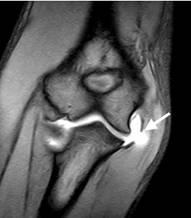

Artro-RM di gomito

Indicazioni:

- sospette lesioni del legamento collaterale ulnare (UCL) parziali e totali.

- sospette lesioni del legamento collaterale radiale (RCL) parziali e totali.

- sospetta osteocondrite dissecante.

- sospetta frattura osteocondrale o condrale.

- sospetta patologia plicale (frangia sinoviale)

- sospetta presenza di corpi liberi endo-articolari.

Tecnica di esame:

- preparazione del paziente, sterilizzando la cute con Betadine ® o analogo disinfettante.

- localizzazione per via palpatoria del repere osseo (spazio articolare omero-radiale)

- introduzione dell’ago tipo “butterfly (23 G) nello spazio precedentemente individuato.

- iniezione tramite siringa pre-riempita con 3-5 mL di soluzione fisiologica mista a contrasto.

- pulizia del sito sottoposto a puntura tramite garza imbevuta di Betadine ®

- posizionamento di un cerotto nel sito di puntura e mobilizzazione dell’arto.